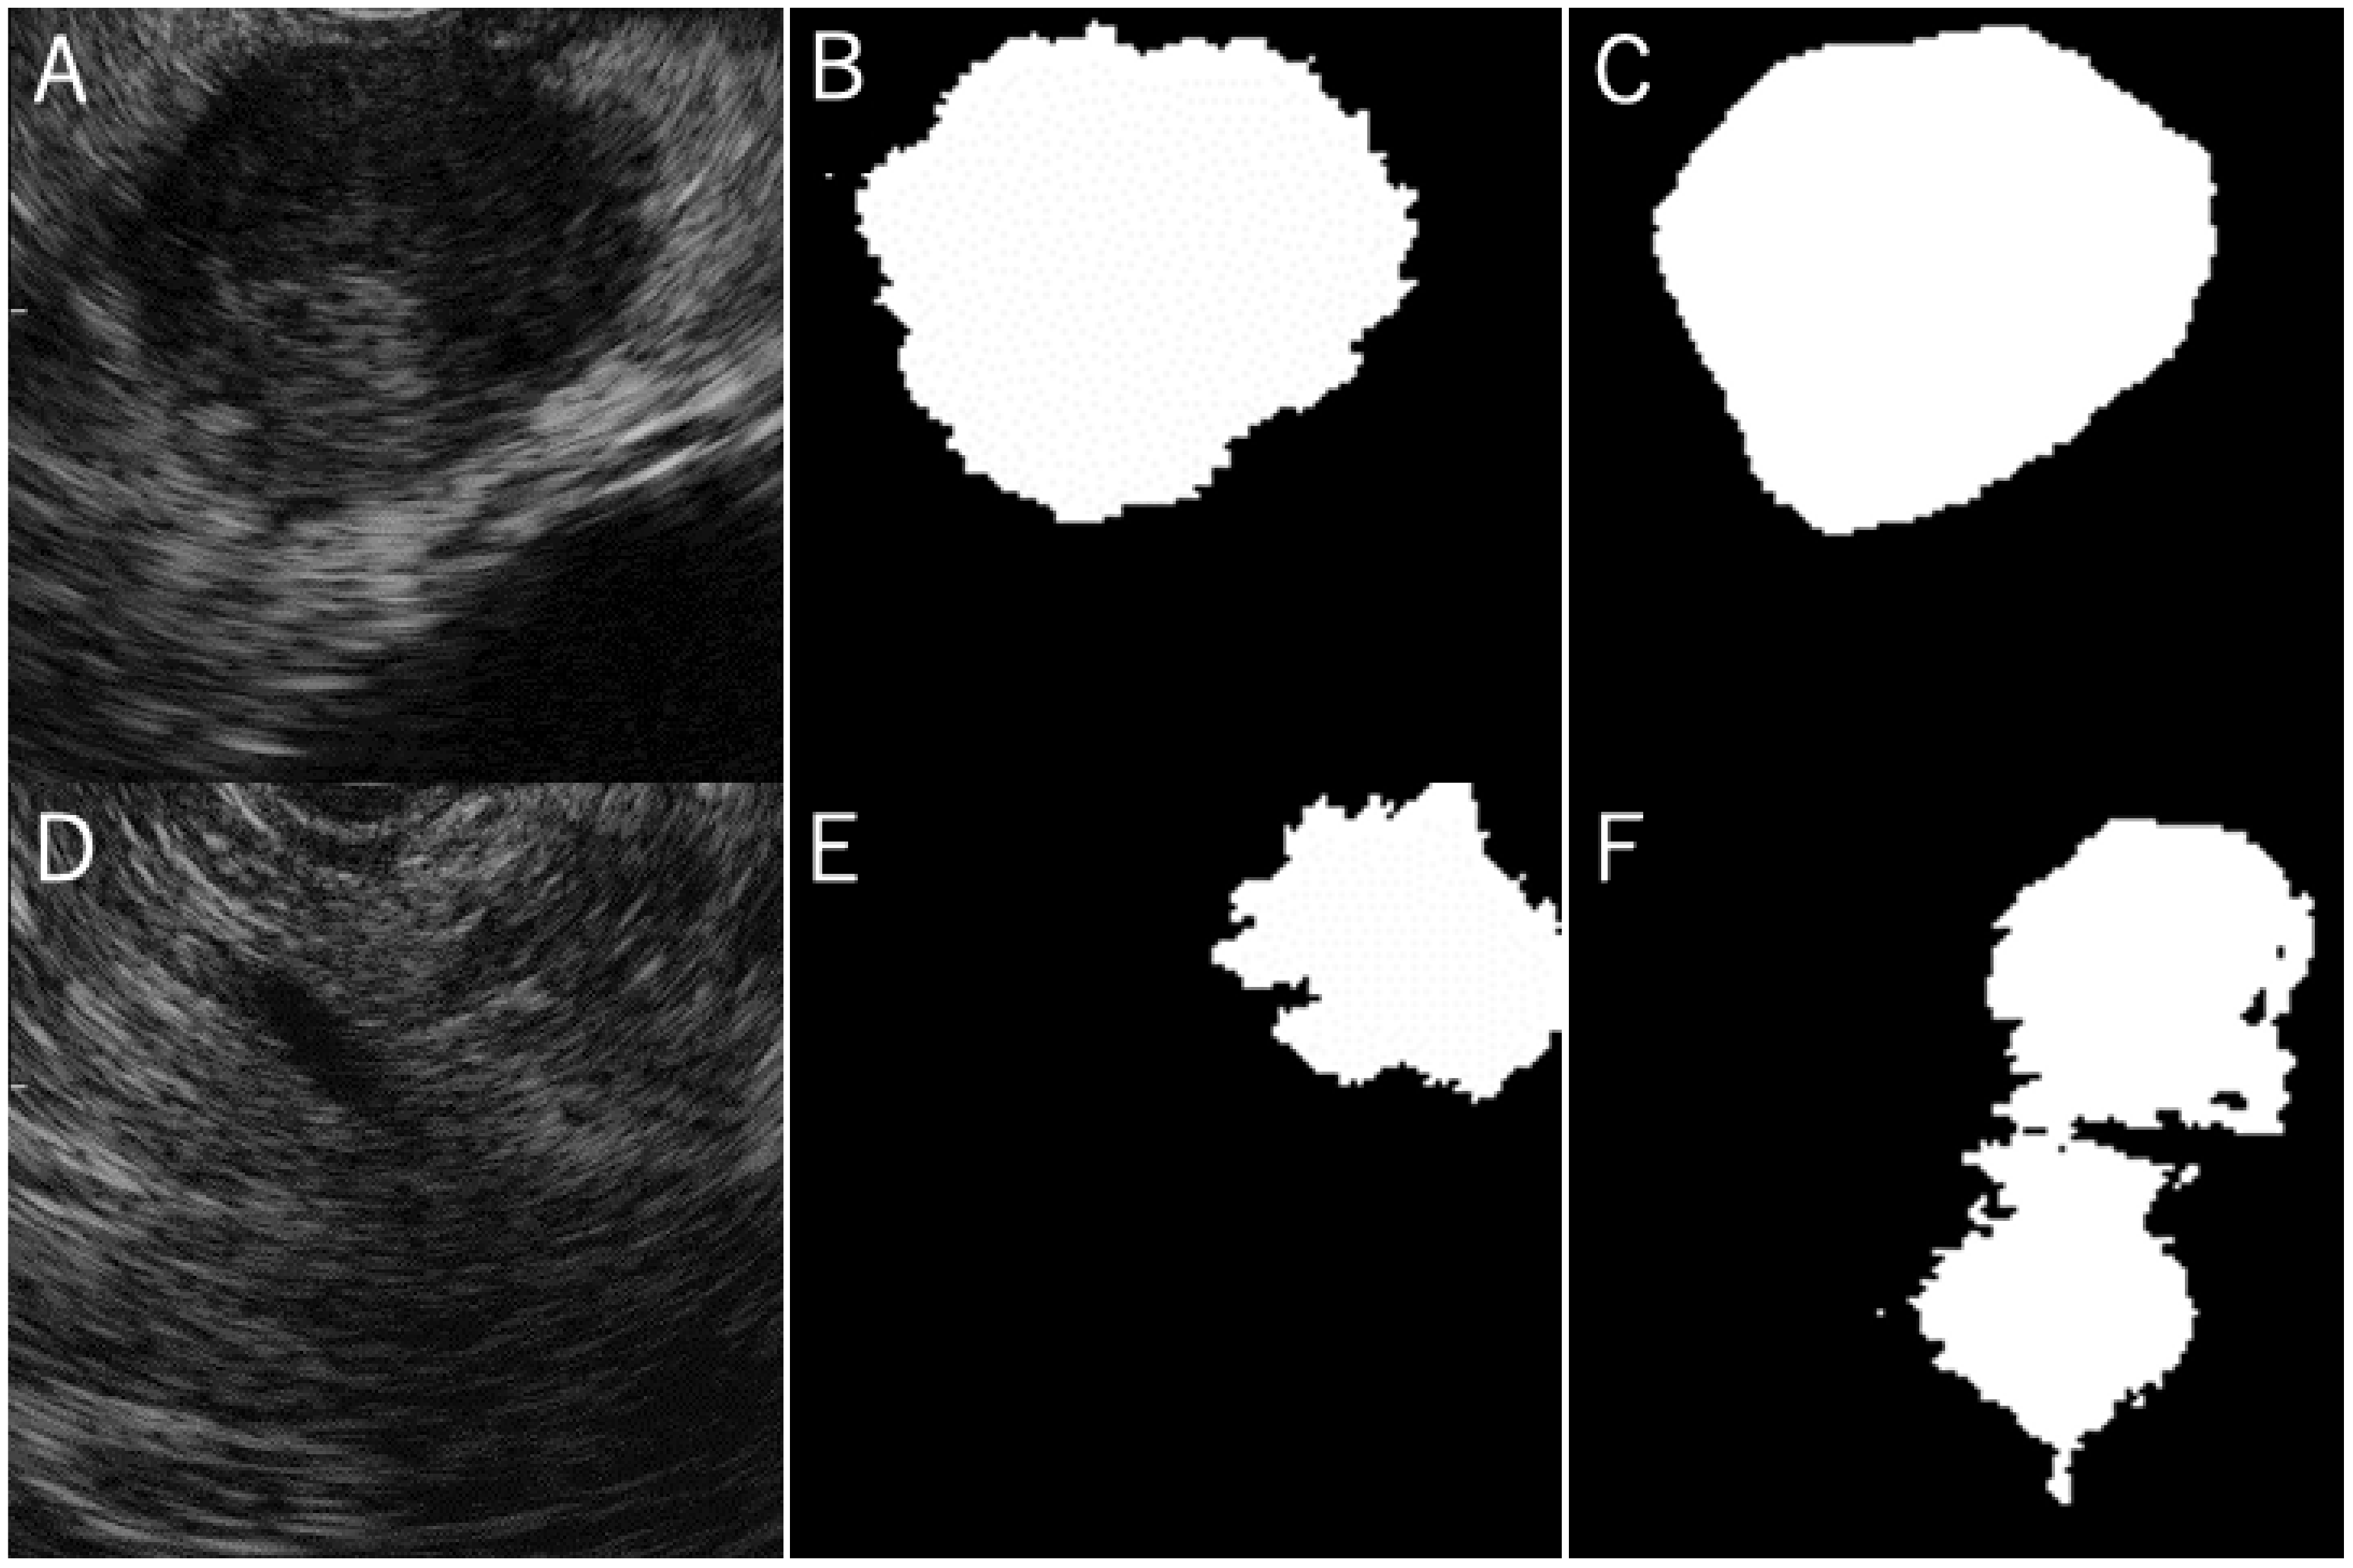

2.3. Preparation of the Training Data Sets

3.2. The Concordance Rate between the Grand Truth Area and Automatic Segmentation Area